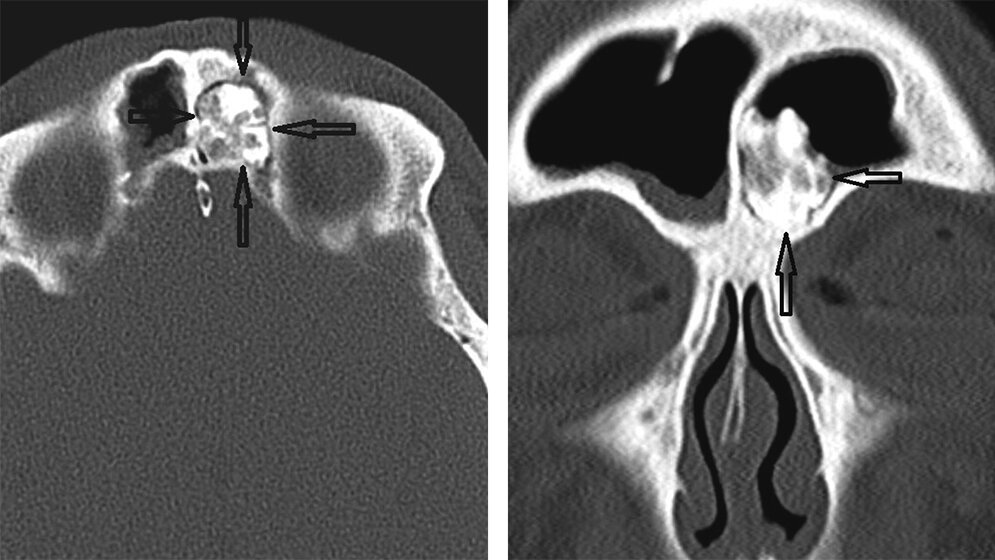

Kraniofaziale Osteome sind langsam wachsende Veränderungen ohne spezifische Wachstumsmuster und seltene Komplikationen. In den meisten Fällen sind die Osteome zufällig bei asymptomatischen Patienten zu finden. Das klinische Verhalten rechtfertigt ein konservatives Vorgehen bei asymptomatischen Läsionen mit radiologischem Follow-up.

Craniofacial osteomas are slow-growing lesions with no specific growth pattern and rare complications. In most cases osteomas are diagnosed incidentally in asymptomatic patients. Their clinical behavior is ill defined and justifies a conservative approach toward asymptomatic lesions with close radiological follow-up.